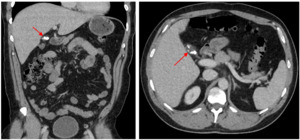

Initial computed tomography scan (CT) showed a thick-walled cystic structure containing stones in the gallbladder fossa which was indicative of chronic inflammation (Figure 1). Subsequent magnetic resonance cholangiopancreatography (MRCP) displayed evidence of a remnant gallbladder containing a 6-mm calculus (Figure 2). Patient was then scheduled for an elective robotic-assisted laparoscopic cholecystectomy for removal of the remnant gallbladder.

Physical examination and blood work narrow down the symptoms to hepatobiliary origin, but imaging allows for a definitive diagnosis to be made. If patients present to the emergency room, they may receive an abdominal CT scan as an initial study. This can display gallbladder dilation, gallbladder wall thickening, and radio-opaque stones.8,11,13 However, if cholecystitis is already suspected, an abdominal ultrasound may be used as a less expensive initial imaging study compared to CT scans. A study by Singh et al. demonstrated ultrasonography accurately identifying calculi in remnant gallbladders in 89% of their sample.14 However, in this study abdominal ultrasound failed to diagnose remnant gallbladder cholelithiasis in 11% of their patients. Similarly, Dikmen et al. displayed a failure to identify the remnant gallbladder in four (36.3%) of their eleven patients.12 The most definitive method of identifying the remnant gallbladder and surrounding anatomy is with an MRCP. In the study performed by Singh et al. MRCP was able to accurately diagnose remnant gallbladder calculi in all but two (4%) of the patients that underwent one.14 In our case, the patient presented to the emergency room initially, so he received a CT scan and an MRCP which led to the final diagnosis of remnant cholecystitis.

_and_axial_(b)_ct_scan_of_stones_inside_the_remnant_gallbladder_with_surroundin.png)